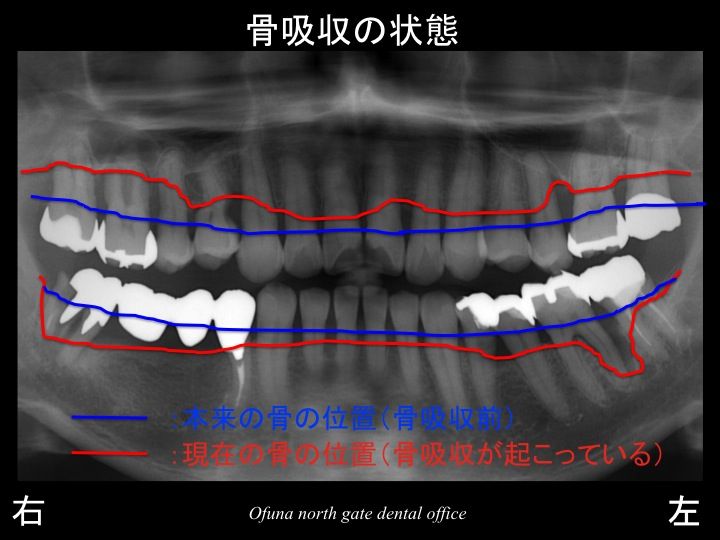

それでは、口腔内全体の歯周病の状態を見てみましょう!

まず骨吸収の状態です。

いつものように 骨吸収の状態を分かりやすくするために

骨吸収の状態を線で書いたのが以下のレントゲンになります。

青線が骨吸収を起こす前の骨の位置です。

赤線は、現在の骨の位置です。

かなりの骨吸収が起こっているのが分かるかと思います。